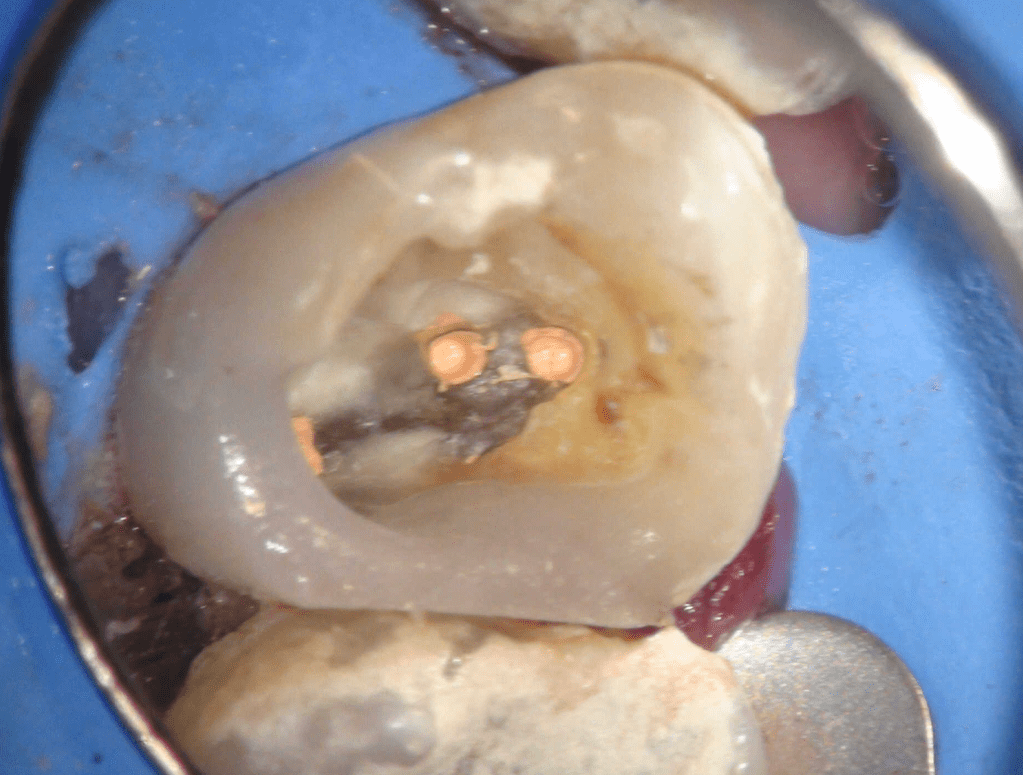

Retratamiento, Localización 4o Conducto